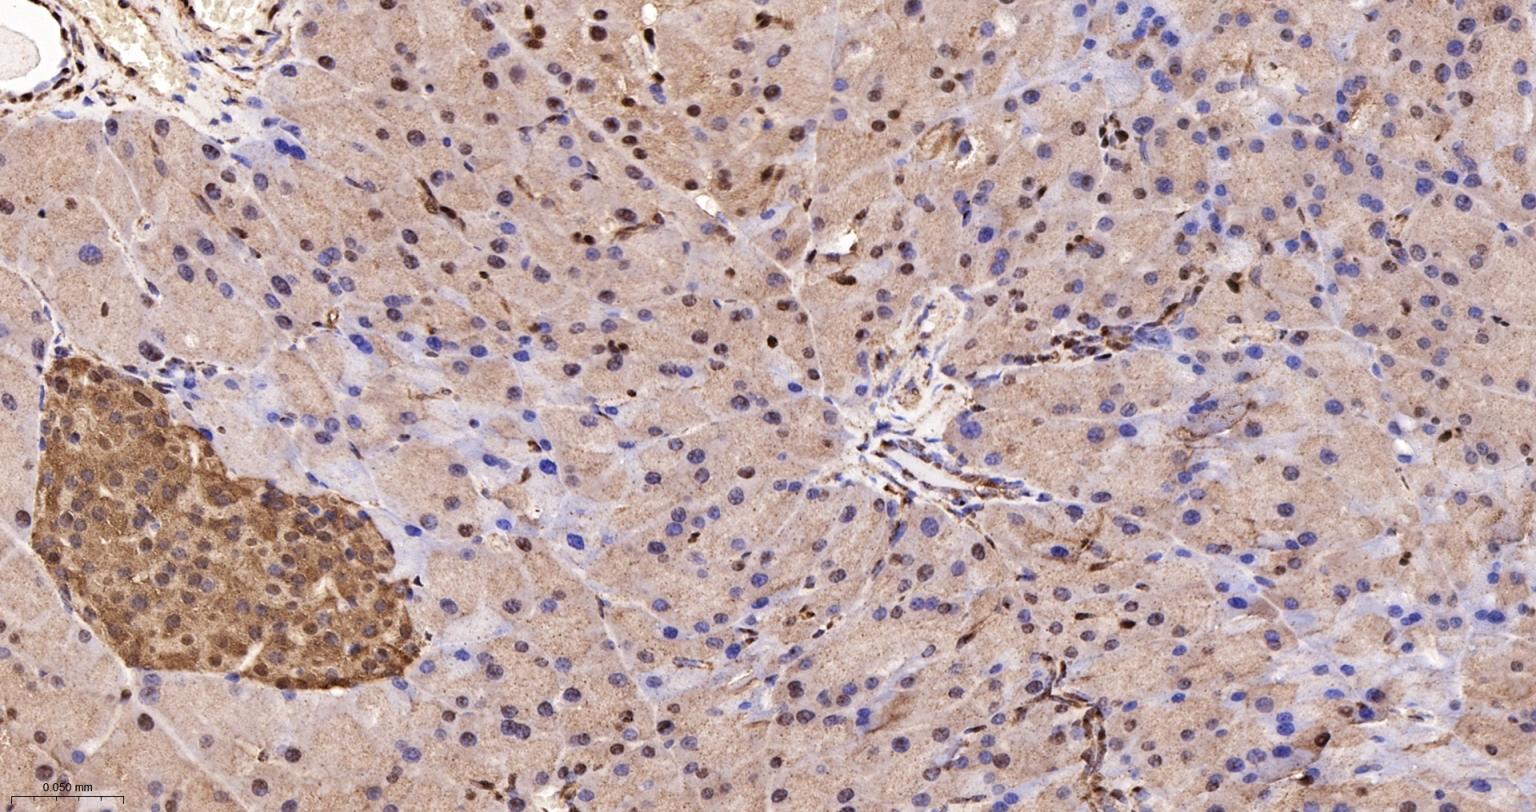

Paraformaldehyde-fixed, paraffin embedded Human Liver; Antigen retrieval by boiling in sodium citrate buffer (pH6.0) for 15 min; Antibody incubation with GAPDH Monoclonal Antibody, Unconjugated(bsm-52262R) at 1:250 overnight at 4°C, followed by conjugation to the SP Kit (Rabbit, SP-0023) and DAB (C-0010) staining.